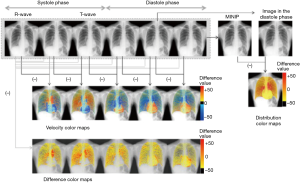

The pulse component, which was originally thought to have a negative influence on the analysis of respiration kinetics, is now known to be related to heart rate, and it was found that relative blood flow distribution could be visualized, as shown in Figure 6. Specifically, it is now known that minute changes in X-ray translucency that occur when the blood that has entered the heart and lung sites is expelled from those sites is reflected in translucency data for target sites.

We have developed an X-ray dynamic imaging technique and a computer image analysis technique as a general initial examination (screening examination) that is able to easily assess respiratory and circulatory physiology and dynamic function. As a result of initial tests on a total of over 100 subjects, we found that additional diagnostic information, such as air trapping in emphysema, anomalistic movement of lung texture in fibrosis, pleural adhesions, and diaphragm kinetics, which could not be obtained using conventional screening examination techniques that rely on still images, could be easily obtained with a relatively high degree of accuracy (2,23). In particular, these results suggest that fDR is useful in monitoring respiratory and circulatory functions in intensive care units during postoperative examinations and emergency examinations using a portable dynamic radiography system (2).

Identifying these techniques as a type of general initial examination (screening examination) using kinetic radiography will allow physicians to obtain more diagnostic data than conventional screening examinations using a method that is far simpler than that used in diagnostic examinations (Figure 7), i.e., these techniques are cost-effective and requires only two times the dose. For example, kinetic and functional data obtained using fDR can provide beneficial diagnostic data that can be used to supplement 3D anatomical data obtained via CT and tissue anatomy data obtained via MRI. Morphological data obtained via X-ray static images are unable to predominate CT 3D data on their own. When performing chest examinations, fDR provides site-specific pulmonary ventilation data that cannot be provided by spirometry, which is the “gold standard” for pulmonary ventilation assessments. Thus, fDR may be an alternative to nuclear medicine, which provides spatial ventilation and blood flow data.